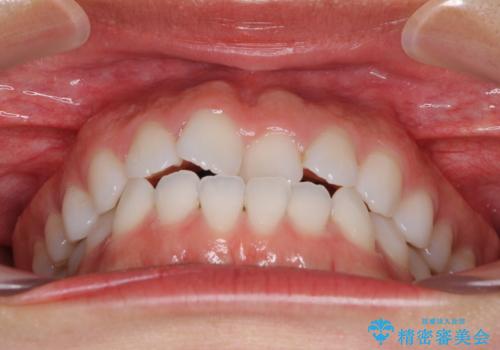

- 上下の前歯の反対咬合を気にして来院された患者様です。

インビザラインを用い、下顎はIPR(歯と歯の間を削る)と歯列全体を後方に移動させ、上顎は前歯を持ち上げることで、反対咬合を改善していくこととしました。

インビザラインによる反対咬合の改善は、上の歯が下の歯を乗り越えていく期間に咬み合わせが非常に不安定となり、治療が長期化することがあります。

こちらの患者様も、一時的に前歯でしか咬めない時期がありましたが、比較的早く咬み合わせが安定し、1年ほどで治療を終えることができました。